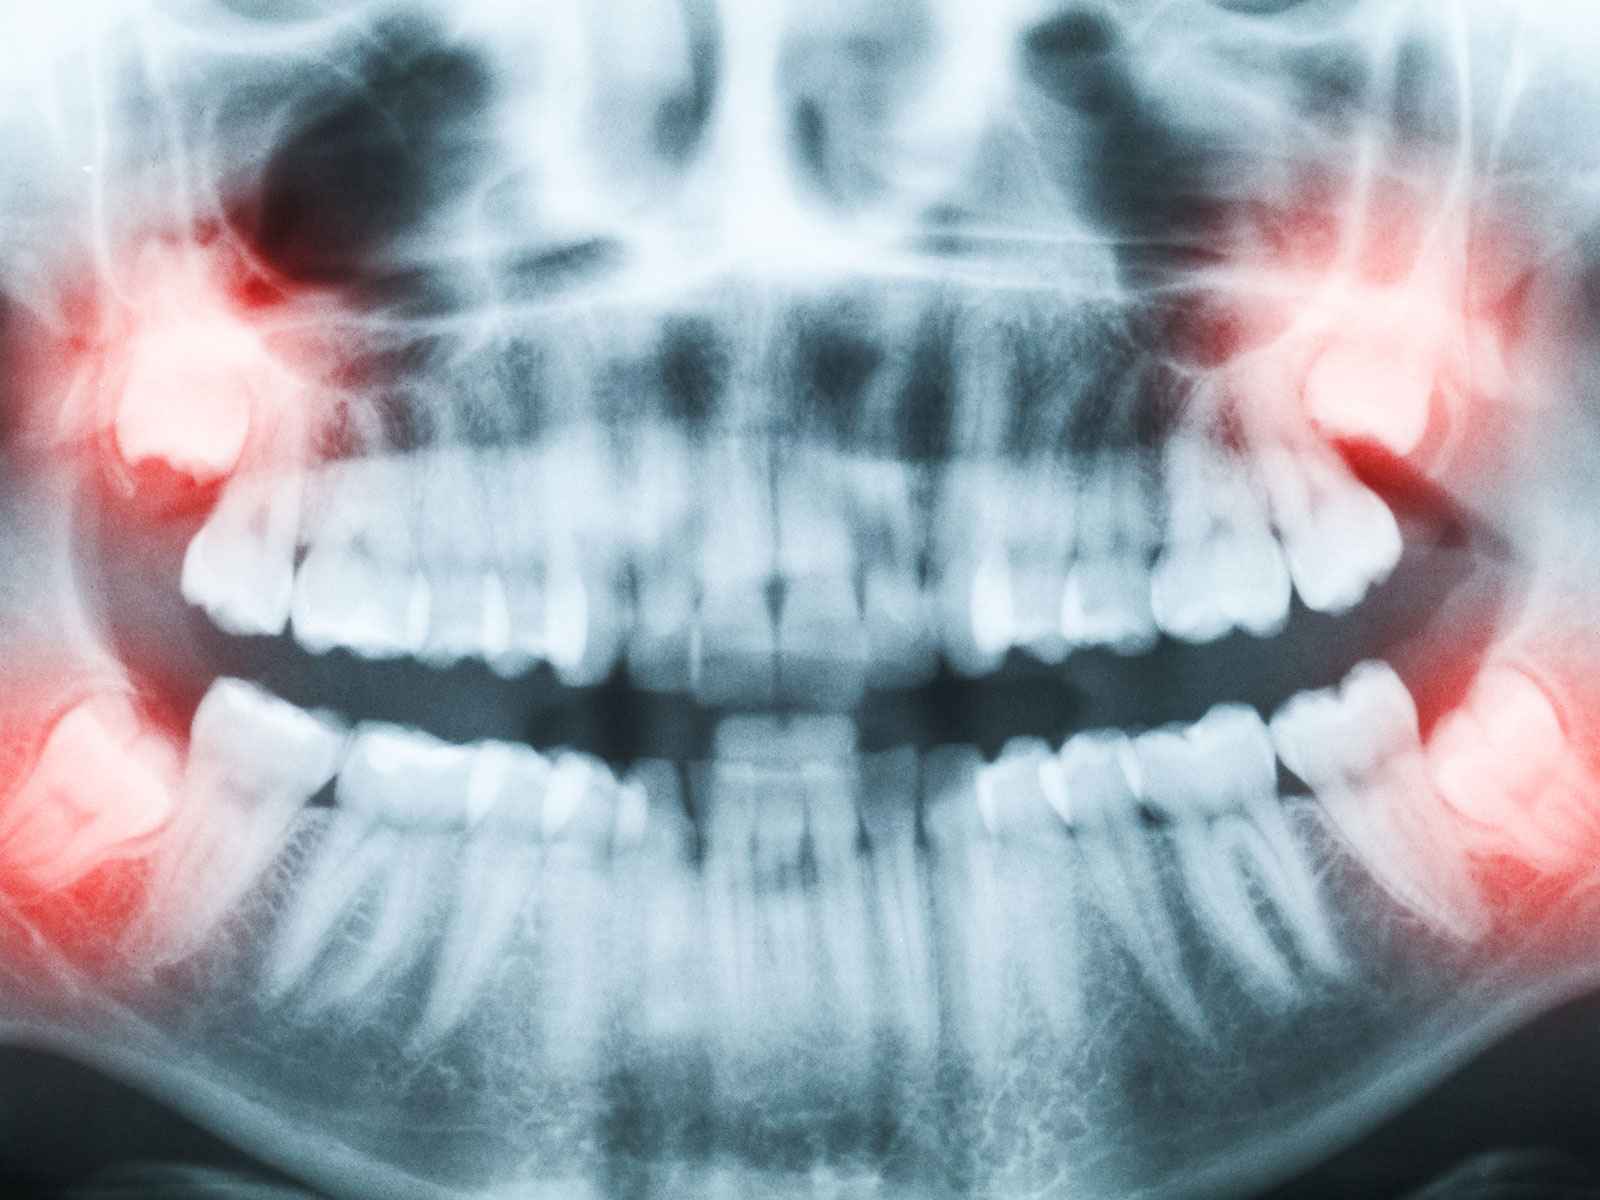

Extraction of Wisdom Teeth

The extraction of wisdom teeth is a procedure to remove one or more wisdom teeth, the four permanent adult teeth in the back corners of the top and bottom of your mouth. Most people have these teeth removed for a number of reasons including pain, discomfort, inflammation, infection or causing damage to neighboring teeth. The surgery is the removal of gum tissue that covers the tooth, detaching the connective tissue that is between the tooth and the bone and finally, removing the tooth and suturing the gum line.